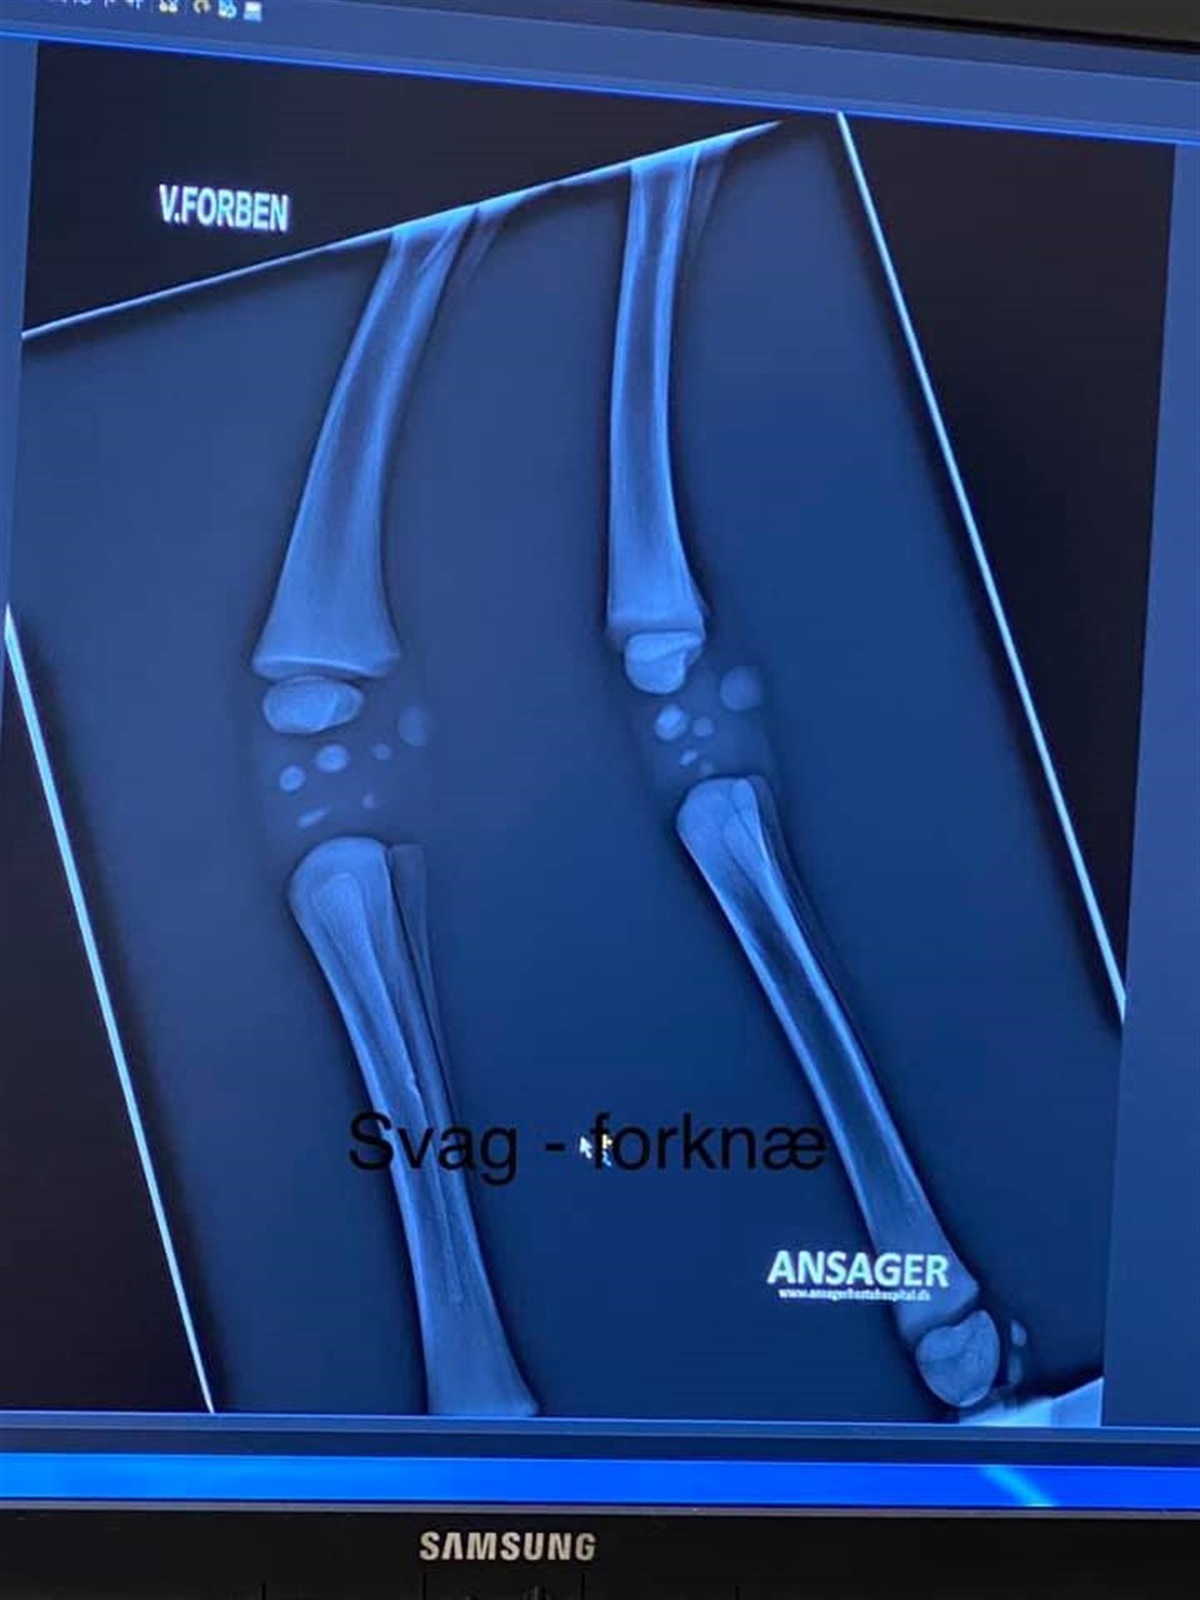

Torsdag morgen (d.18/3) ringer hun til Ansager Dyrehospital, som anbefaler hende at få de to hingsteføl røntgenfotograferet for at tjekke om forknæ og haser er underudviklet.

Røntgenbillederne viste desværre stærkt underudviklede forknæ og haser hos begge føl, og der var ikke noget at gøre.

Røntgenbilleder af det ene føls forknæ. Bemærk den mangleden knoglevækst. Foto: privat